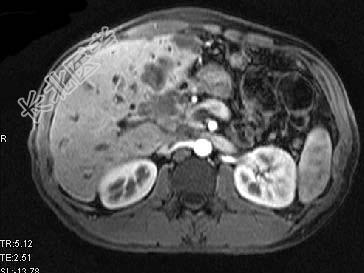

- 单项选择题根据所提供的图像,最可能的诊断是 ( )

A、肝囊肿

B、肝脓肿

C、先天性胆管扩张

D、胆管细胞癌肝内转移

E、以上都不是